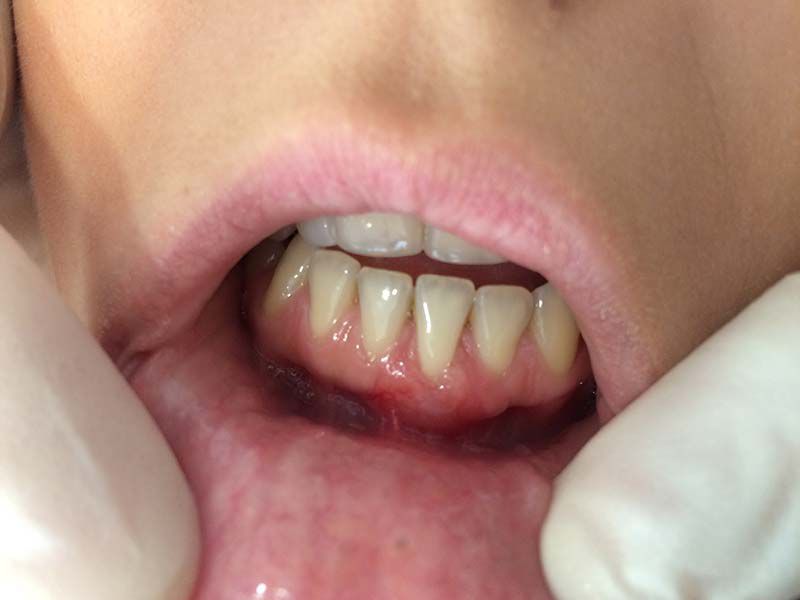

Especialización dedicada al cuidado de las encías. En este caso, se ha realizado un injerto de conjuntivo en el incisivo central inferior